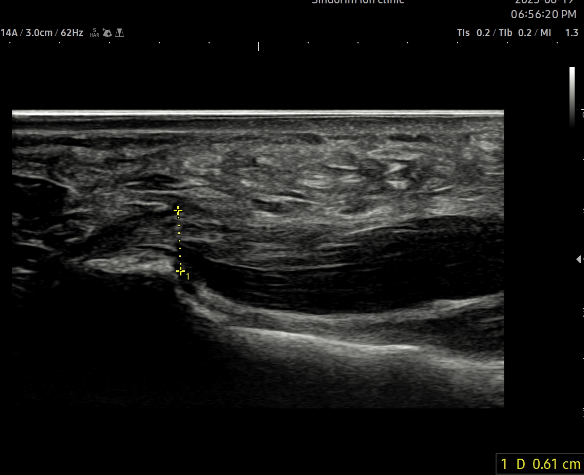

- 치료기간 : 25 .6 .19 ~ 25 . 10 . 23

- 치료횟수 : 15 회 (아피톡신+극초단파)

치료 전 (족저근막 두께 0.44~0.61cm)

치료 후 (족저근막 두께 0.33~0.36cm)